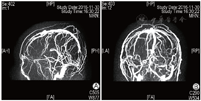

2016年8月1日患者行第1周期IVF-ET,采用黄体期短效长方案促排卵,促性腺激素(Gn)用药13 d、Gn总量2925 IU,扳机前一日雌二醇水平>11 010 pmol/L(本院检测值上限),取卵2枚,成胚1枚(6CII),因子宫内膜因素未行新鲜胚胎移植。2016年11月12日行第2周期IVF-ET,周期第2日卵泡刺激素(FSH)为4.87 IU/L,黄体生成素(LH)为6.84 IU/L,雌二醇为194 pmol/L,孕酮为3.21 nmol/L。采用短方案促排卵,皮下注射醋酸曲普瑞林(达必佳,德国辉凌制药)0.05 mg、肌内注射尿促性腺激素(hMG,珠海丽珠制药)150 IU+尿促卵泡素(丽申宝,珠海丽珠制药)150 IU启动。Gn第6日雌二醇水平>11 010 pmol/L,逐渐减少Gn用量。Gn持续使用11 d、Gn使用总量为2550 IU。周期第13日优势卵泡(直径>14 mm)达到扳机标准,B超示双侧卵巢明显增大,直径>14 mm卵泡20枚,稀释后查雌二醇水平为110 117 pmol/L,当晚肌内注射人绒毛膜促性腺激素(hCG,珠海丽珠制药)6000 IU。扳机后36 h行取卵术,获卵16枚,过程顺利。患者于取卵后12 h开始出现恶心、呕吐、腹胀,伴胸闷、憋气,尿量较前减少,体温正常,于取卵后当日晚间急诊就诊,急查白细胞计数(WBC)为21.34×109/L,红细胞比容(Hct)为55.30%,全血C反应蛋白(CRP)为16.59 mg/L,D-二聚体为670.00 μg/L,血钠水平为131.0 mmol/L,随机血糖(Glu)为14.48 mmol/L,妇科B超提示右侧卵巢大小约15.2 cm×12.2 cm×9.2 cm,左侧卵巢约13.8 cm×8.1 cm×6.8 cm,腹、盆腔内探及液性回声,较深处约4.1 cm,考虑重度OHSS。予以补液、抗凝等治疗,症状未见明显缓解。常规IVF授精,共获得4枚有效胚胎(3枚8CII、1枚7CII),冷冻保存。取卵术后第4日,患者突然出现肌力下降并跌倒,左侧肢体活动不灵,伴嗜睡,急症收入院。入院时血压120/91 mmHg,呼吸26次/min,心率120次/min,体温36.8 ℃,查体示瞳孔等大等圆,直径约3 mm,对光反射存在,双眼向右侧凝视,口角右歪,腹膨隆,左侧上下肢肌力为0级,右侧肌力5级,右侧肌张力正常。急查WBC为18.83×109/L,Hb为160 g/L,Hct为46.40%,D-二聚体为4 090.00 μg/L,纤维蛋白原(FIB)为4.86 g/L,CRP为12.42 mg/L,白蛋白为28.50 g/L,总胆固醇(TC)为7.25 mmol/L,甘油三酯(TG)为3.63 mmol/L,行颅脑CT提示矢状窦、直窦、双侧横窦、双侧乙状窦及额部部分静脉走行区密度不均匀增高X线计算机断层摄影(CT)值为70~80 Hu,考虑多发静脉窦和静脉走行区密度增高,血栓可能(图1),行颅脑磁共振静脉血管造影(MRV)提示双侧大脑大静脉-直窦、窦汇、双侧横窦显示不清,上矢状窦及其属支略扩张,考虑静脉血栓形成可能性大(图2)。入院诊断为“肌力下降原因待诊:颅内血栓形成?、OHSS(重度)、Ⅱ型糖尿病、高血压病、高脂血症、低蛋白血症、乙肝小三阳、原发性不孕症、IVF术后(2次)”。入院后立即给予甘露醇(天津百特医疗)降颅压及低分子肝素抗凝治疗,并在局部麻醉下行经股动脉插管全脑动脉造影术+全脑血管造影+静脉窦球囊扩张+溶栓及取栓术。手术顺利。术后造影提示静脉窦较前明显通畅,上矢状窦、横窦及乙状窦均显影,脑血管回流较术前明显改善。术后继续予以补液、抗凝、降颅压、改善脑循环等对症治疗。患者恢复好,复查血WBC、D-二聚体、Hct、雌二醇水平逐渐恢复正常,于2周后顺利出院。出院后继续予以低分子肝素钠注射液(法安明,美国辉瑞药业)5000 IU皮下注射 qd抗凝治疗,定期复查,未见明显异常。

A示矢状位; B示冠状位